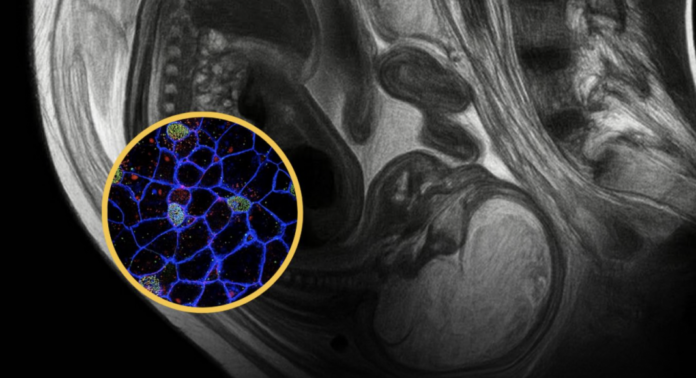

Gjatë shtatzënisë, ndodh një shkëmbim qelizash përmes placentës: jo vetëm qelizat e fetusit kalojnë tek nëna, por edhe qelizat e nënës migrojnë në trupin e fetusit.

Këto qeliza janë zbuluar në gjak, lëkurë, mëlçi, palcë kockore dhe madje edhe në tru. Ato mund të përshtaten me inde të ndryshme dhe mendohet se luajnë rol në rigjenerimin e tyre dhe në sistemin imunitar.